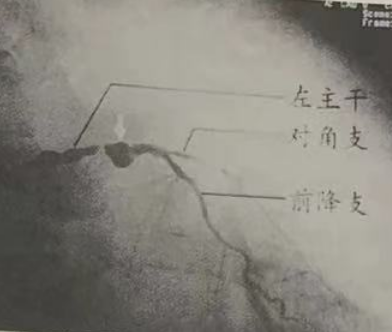

图2

左主干远端严重狭窄,左前降支起始段明显呈“瘤样”向外扩张,突出于正常血管壁以外。此为冠状动脉瘤